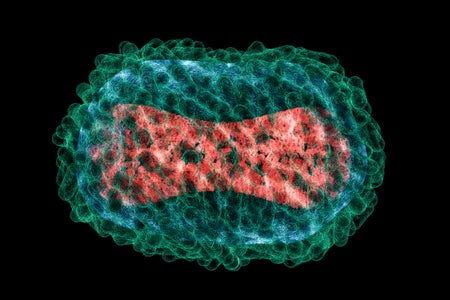

What Is Monkeypox, the Virus Infecting People in the U.S. and Europe?

A microbiologist explains what is known about this smallpox cousin